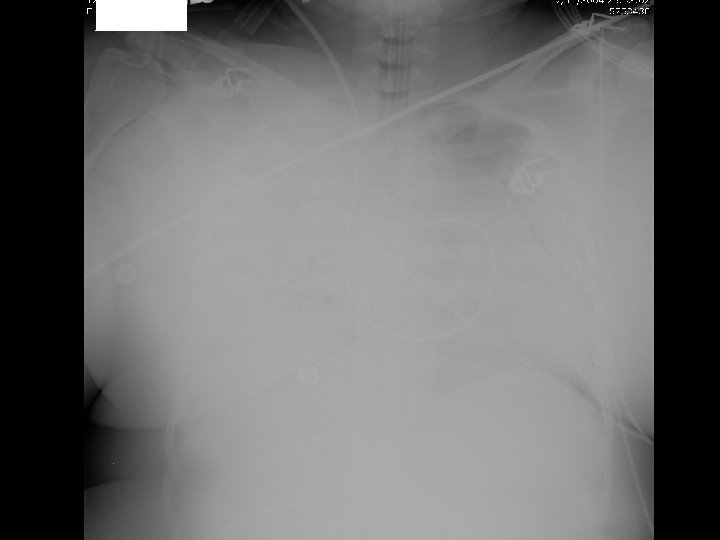

• Diffuse bilateral infiltrates – Patchy, confluent – Alveolar, ground ‐ glass • In contrast to CHF, no prominence of. . – Cardiomegaly – Pleural effusion – Widened vascular pedicle

ARDS: Chest Radiograph Criteria • Radiographic findings not attributable to: – Chronic changes – Atelectasis – Mass – Pleural effusion